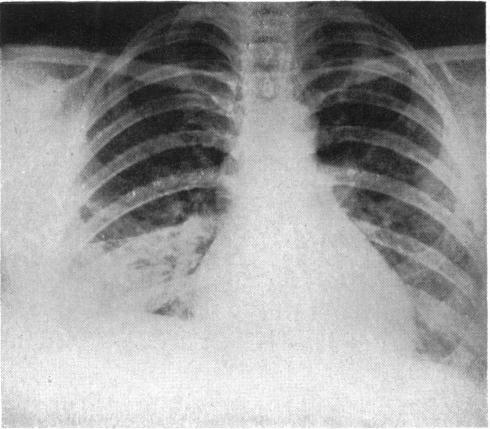

Atypical pneumonia.

Br Med J. 1950 Dec 30;2(4695):1457-61. doi: 10.1136/bmj.2.4695.1457.